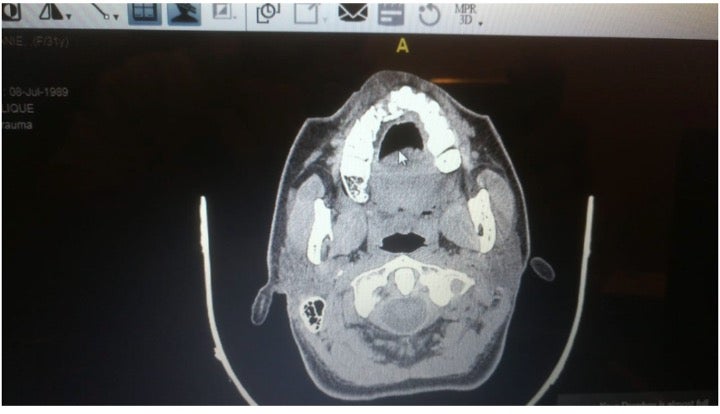

تظهر الأشعة السينية كسرا في عظم الفك العلوي لمتظاهرة بعد أن أصيبت برصاصة مطاطية.